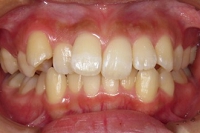

CASE1

前歯の歯並びが悪いのが一番気になります。

右側では良く噛めません↓(16歳/女性)

概要・担当医コメント:叢生・右側咀嚼障害↑

マルチブラケット装置/動的治療期間26ヶ月(23回)

/費用概算:60万円

高校の部活も矯正も両方頑張れたそうです。

上顎右側の小臼歯を1本のみ抜歯させていただき,あとは上下の歯列アーチ形態の修正にて矯正できました。